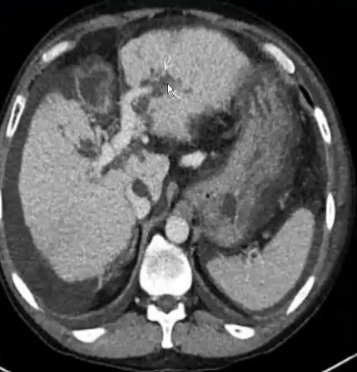

❖ 肝硬化伴门脉高压症:多发性肝胆道周围囊肿

❖ 尽管胆道周围囊肿通常被认为是无临床症状,囊性扩张似乎是梗阻性黄疸进展的原因